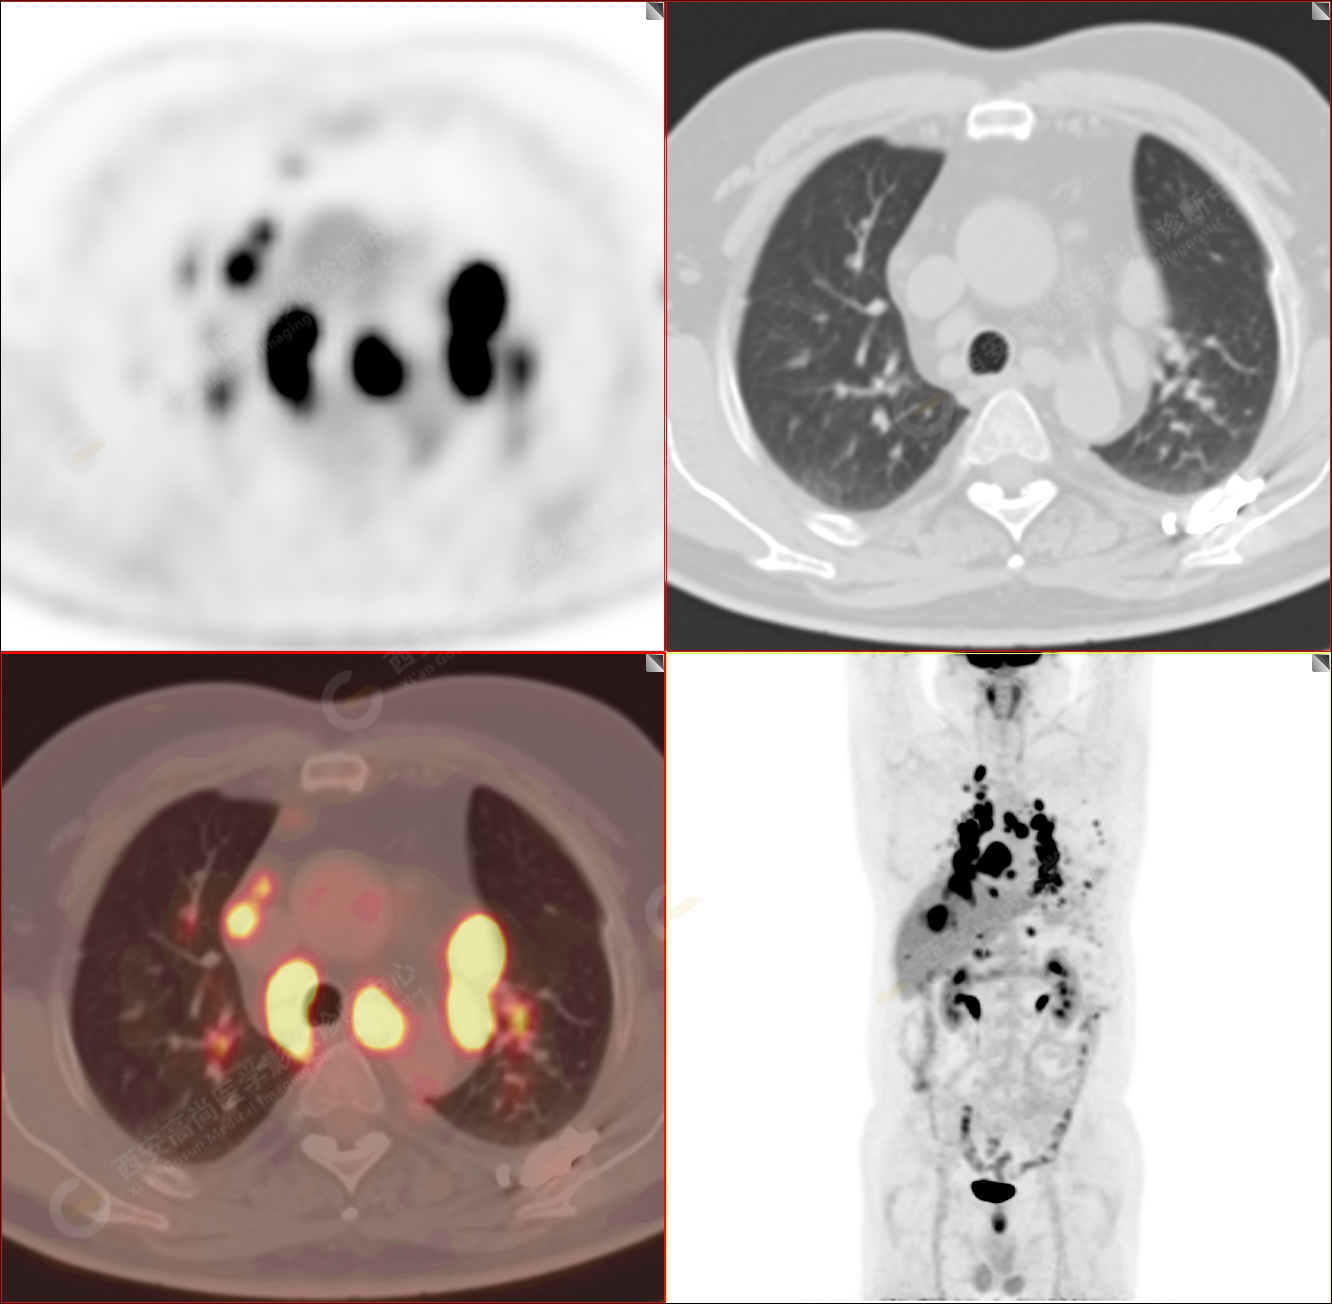

PET/CT圖像